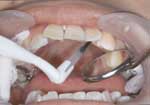

각 브라켓의 베이스를

microetcher (Danville Engineering Inc.)를 사용하여 sandblasting

처리하여 차후 접착제의 retention을 증가시켜준다. 브라켓

베이스에 광중합형 레진(Transbond XTTM,

3M Unitek)을 적당량 올리고 각 설측 치면에 위치시킨다.

이 단계에서는 pressure를 주지 않는다.

브라켓 슬롯 guiding

plate를 사용하여 치면에 적합되도록 개개 브라켓의 위치를

조정한다. 이 과정에서 브라켓의 angulation과 inclination이

확정된다.

브라켓 위치가 확정되면

브라켓 주위의 과다 레진을 explorer로 제거하고 광중합을

시행한다. 금속 브라켓의 경우 치축 방향으로 교합면에서

10초, 치은면에서 10초씩 light를 조사한다. 한편, passive